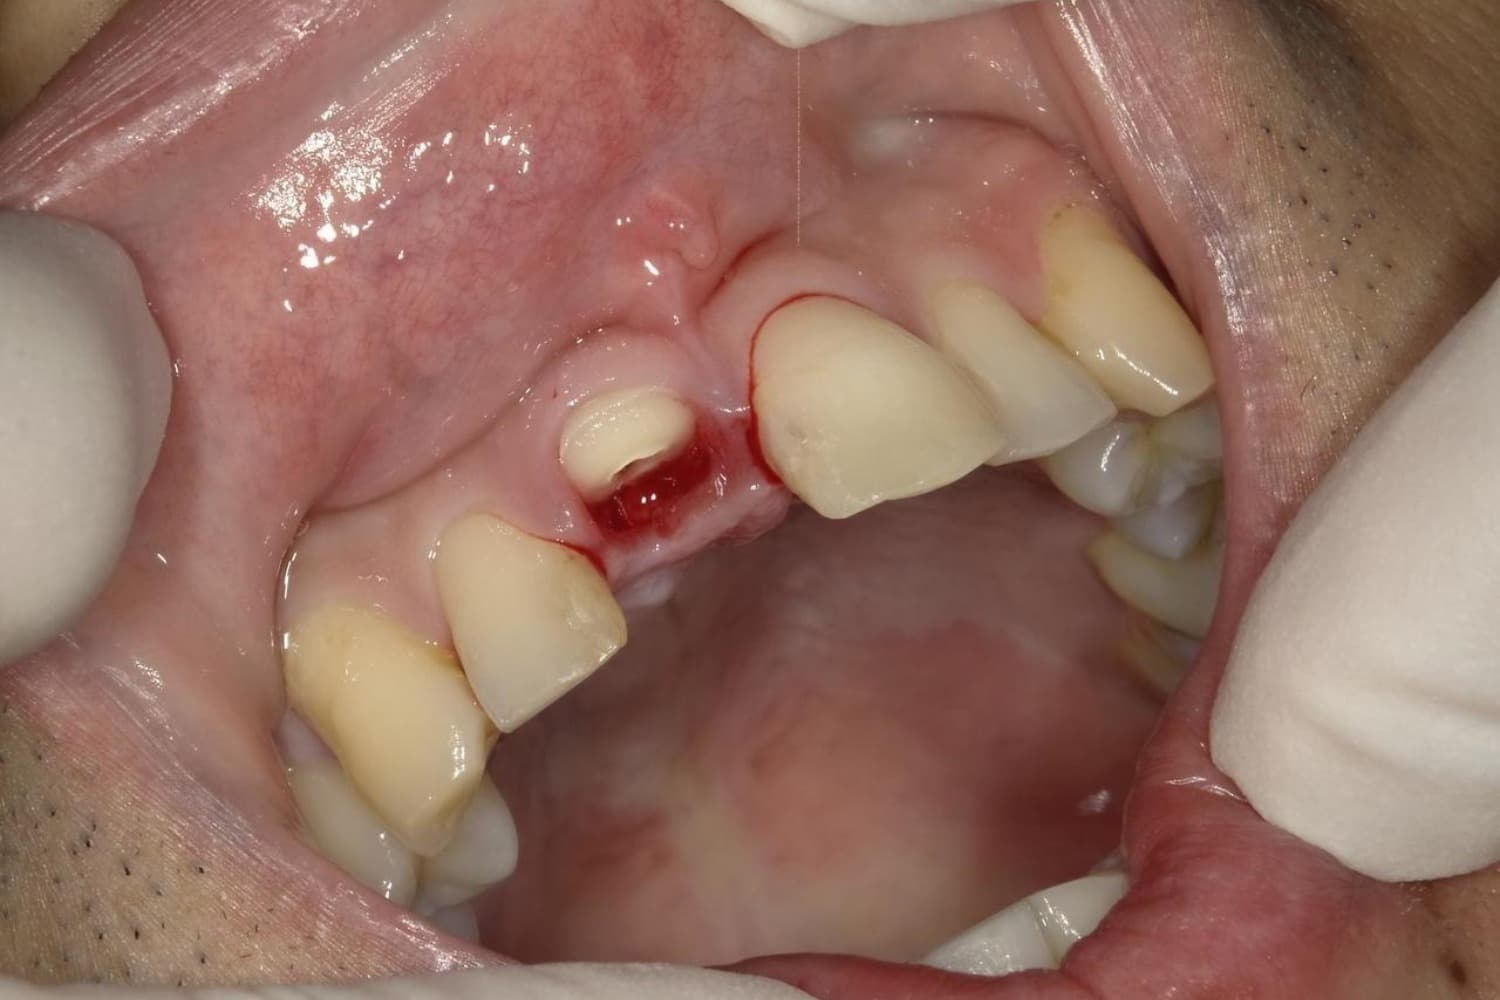

歯根破折した前歯のインプラント治療(30代男性)

Before

外傷によって歯根破折した前歯を抜歯してインプラント治療をおこなう(当日に仮歯の装着までおこなう)。

年齢

30代

性別

男性

主訴

外傷によって歯根破折している。

治療期間

2ヵ月半

治療回数

6回

費用

385000円(税込) 費用の内訳: 【インプラント基本料】330000円(税込み) 基本料金に以下を含む ・フィックスチャー及び手術費用 ・投薬費用、 ・レントゲン費用 ・インプラント上部費用(アバットメントおよびジルコニアクラウンの費用用) 【オプション費用】 ・抜歯即時埋入・即時負荷加算(プロビショナルレストレーション費用・人工骨費用・暫間アバットメント費用・抜歯費用を含む)55000円(税込)

副作用・リスク

・手術後に痛み・腫れ・出血・合併症等を引き起こす恐れがあります。 ・噛む感覚がご自身の歯と異なることがあります。 ・見た目がご自身の歯と異なる場合があります。 ・手術後もメインテナンスを続けないと、インプラントが抜け落ちてしまう恐れがあります。